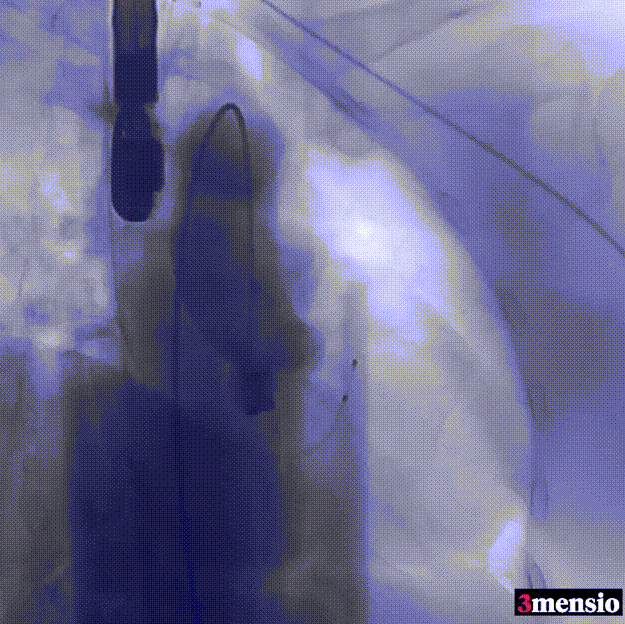

手术过程回顾:

患者全麻后,右侧股动脉建立主入路,主动脉根部造影显示主动脉瓣无明显钙化。心室内轻中量反流,主动脉及心脏情况整体较为稳定,根据术前策略预装23mm瓣膜。超硬置入左心室后,因超硬压迫无冠瓣叶导致急性反流,病人血压降至40mmHg,遂迅速将输送器送入主动脉根部,快速释放瓣膜后,病人血压恢复至正常。瓣膜脱钩后造影显示左冠开口存在一定狭窄,IVUS评估左冠开口狭窄约60%,符合PCI指征,植入开窗支架改善狭窄,最终再次造影加IVUS评估左冠开口,确定狭窄解除。

主动脉根部造影

输送器定位